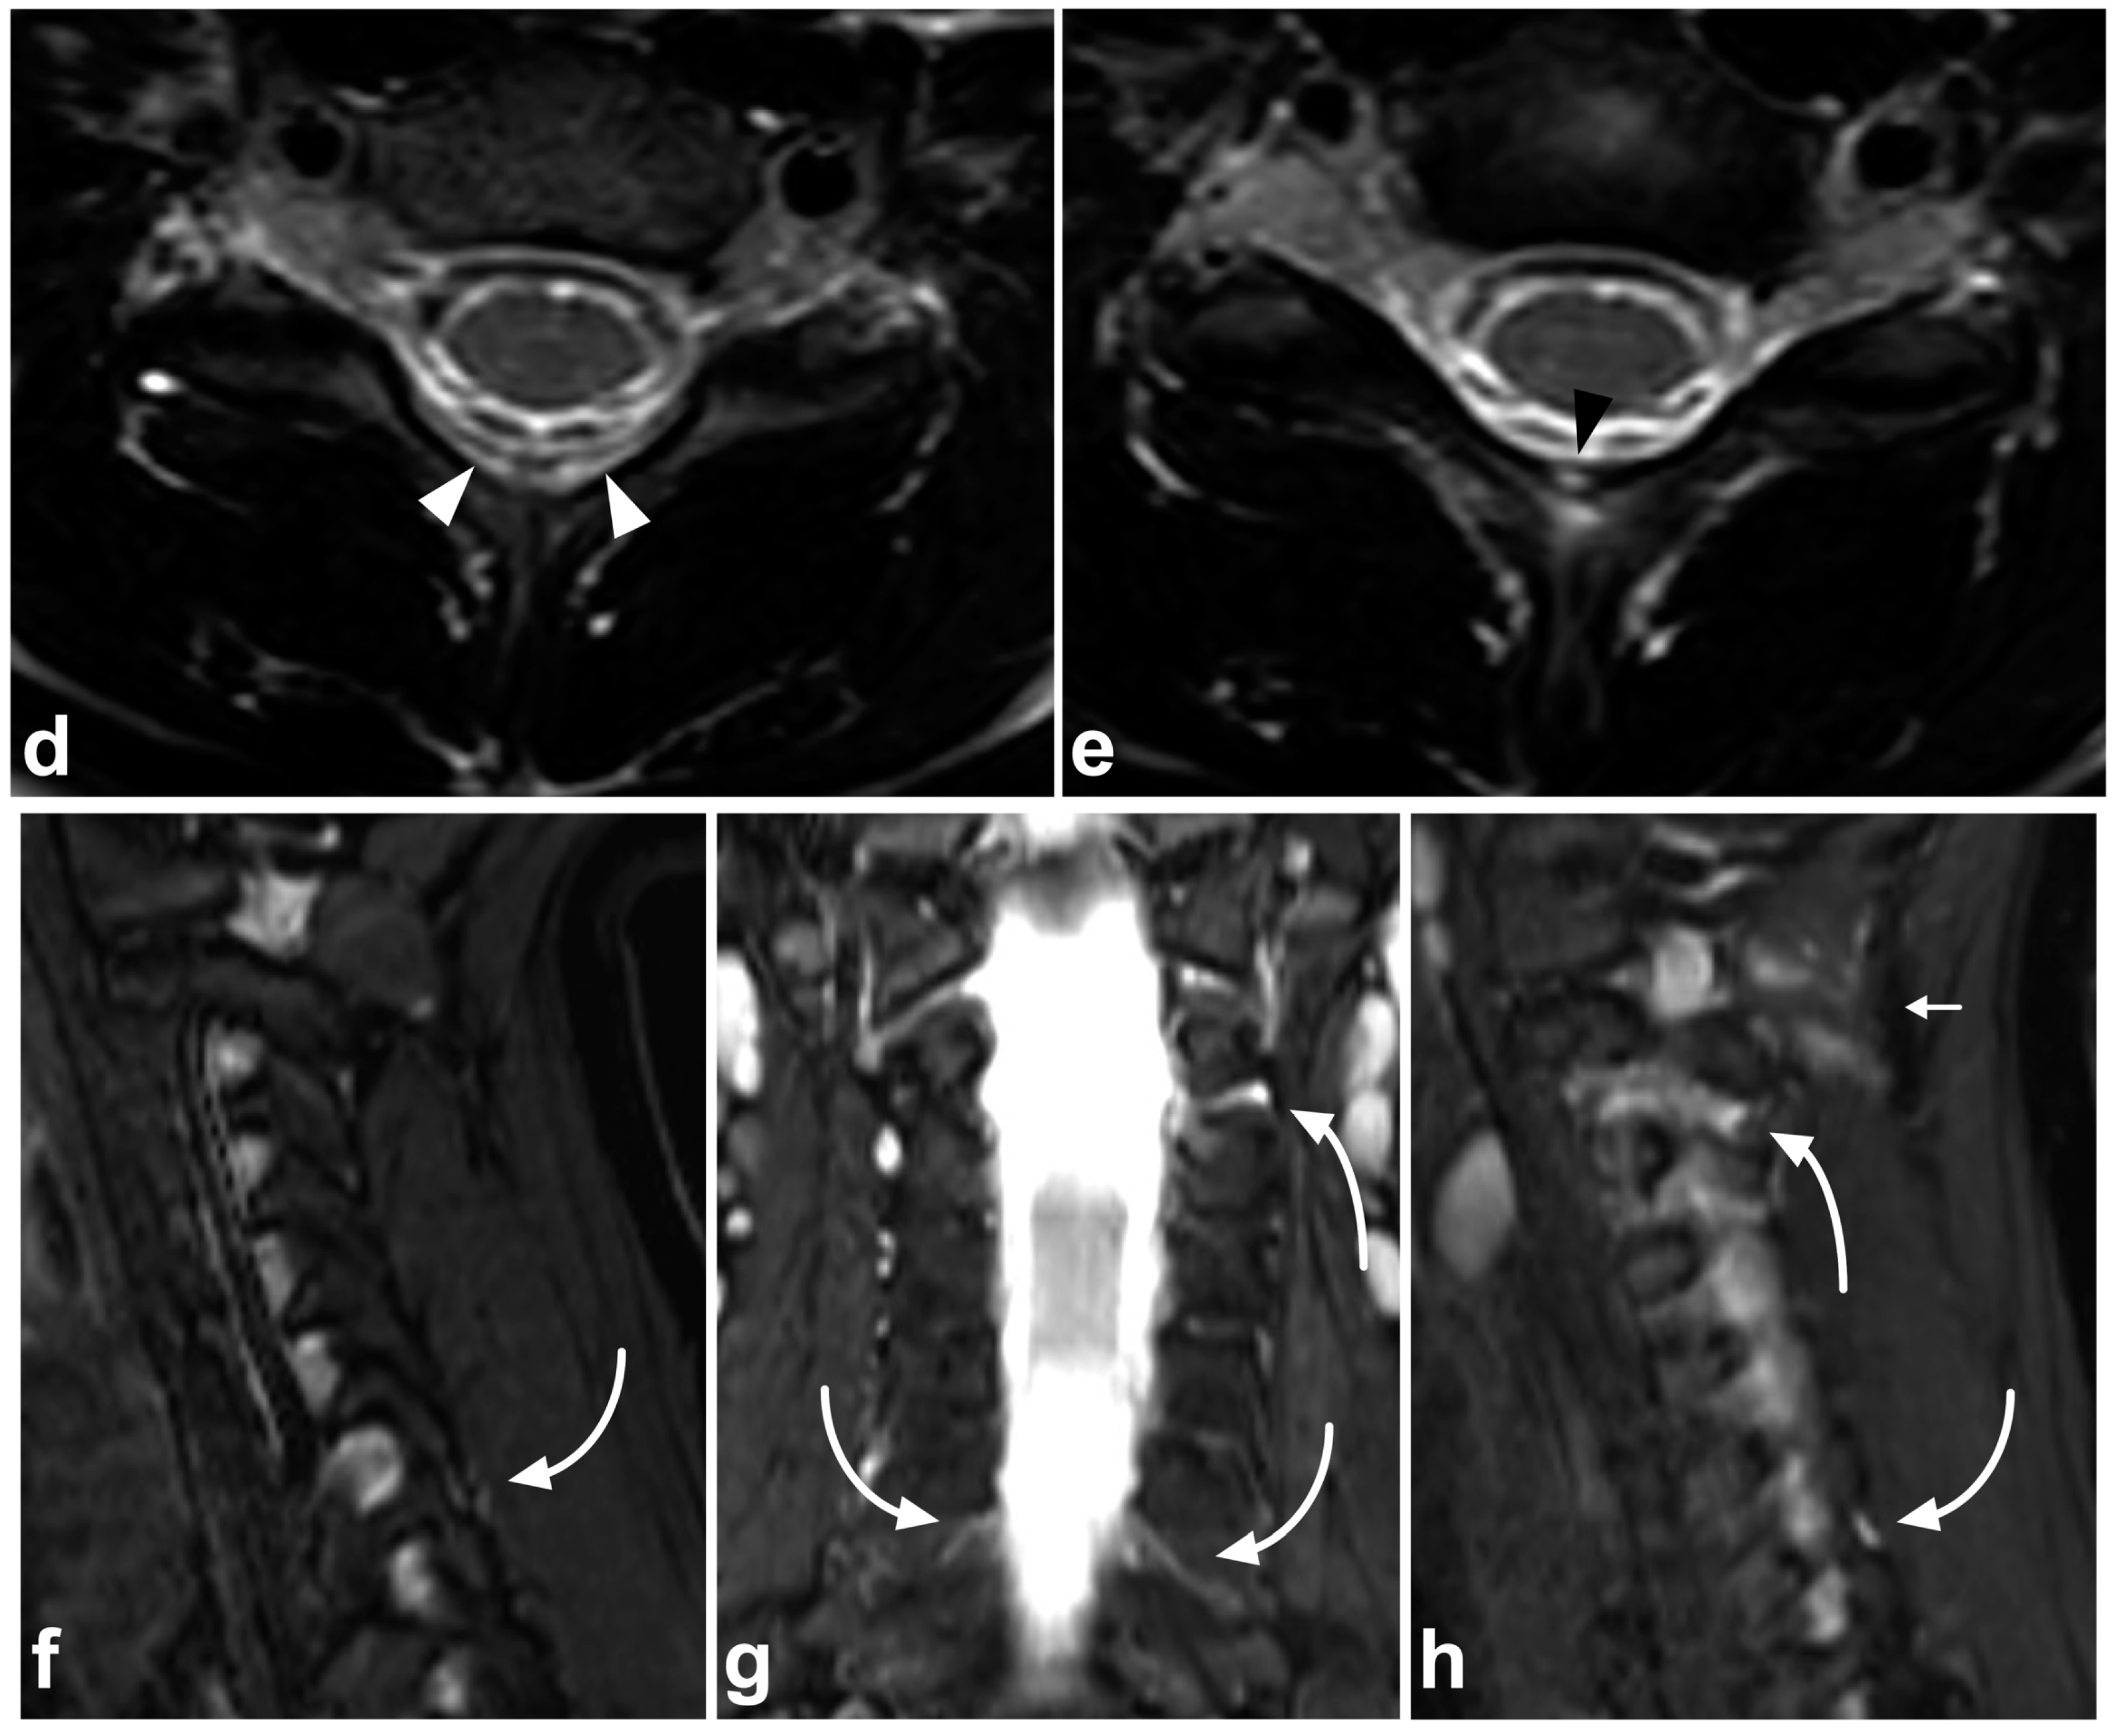

Figure 9.

(a) Sagittal STIR. (b) Sagittal T2-weighted. (c) Sagittal T1-weighted. (d,e) Axial T2-weighted, two adjacent slices at the level C6/7 (line on the image (c)). (f) Right-sided off-midline sagittal STIR. (g) Coronal STIR. (h) Left-sided off-midline sagittal STIR. A 9-year-old female, flexion injury in a trampoline accident. On level C2/3, there is slight edema in the posterior atlantoaxial membrane (PAAM), rectus capitis posterior major muscle, nuchal ligament, and adjacent deep cervical fat tissue (small white arrows). On level C6/7, we see more prominent edema of the interspinous and supraspinous ligaments (white arrows); there is a partial tear in the interspinous ligament. At this level, the ligamentum flavum is inhomogeneous (black arrowheads) due to a partial tear but without loss of continuity. A thin hematoma can also be seen between the flavum and posterior arch of C7 (white arrowheads, image (d)). Minor facet joint injury is also present; a small amount of fluid and edema can be seen at the left C2/3 facet joint and the posterior parts of both facet joints at level C6/7 (angled arrows). In addition to the PLC injury, there are compression fractures at the anterior parts of the vertebral bodies C7/Th3 (white asterisks). This is also a typical finding in flexion injuries of the cervical spine. The findings presented are highly unlikely to lead to instability, demanding a surgical fixation. However, this case demonstrates MRI’s power to directly assess the different stabilizing structures of the spine.